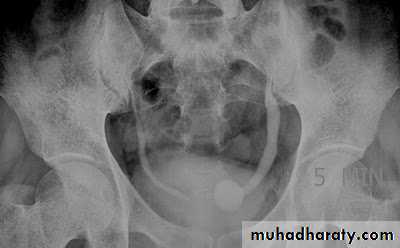

37- Phlebolith